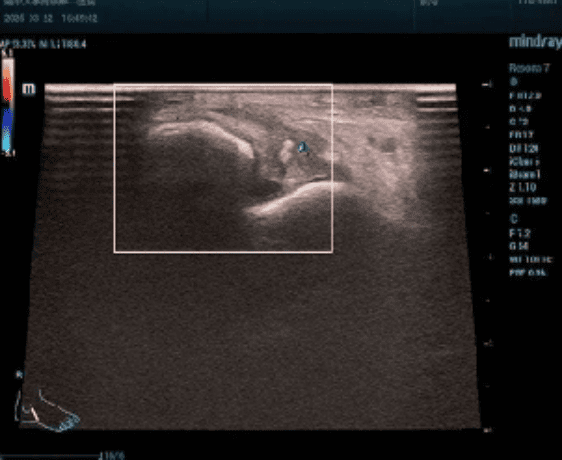

我院是整个衡阳市唯一一家开展经直肠肛管超声检查的医院, 于2025年7月开展至今,已经完成近20余例,获得患者及临床科室的一致好评。

该技术优势突出:探头紧邻靶区,成像清晰精准,能清晰显示肛管直肠壁各层及周围组织细节,对微小病变检出率高,尤其利于早期病变发现;无辐射损伤,适合多次复查及孕妇等特殊人群;可为直肠癌分期、疗效评估及随访提供关键信息,助力个体化治疗决策。